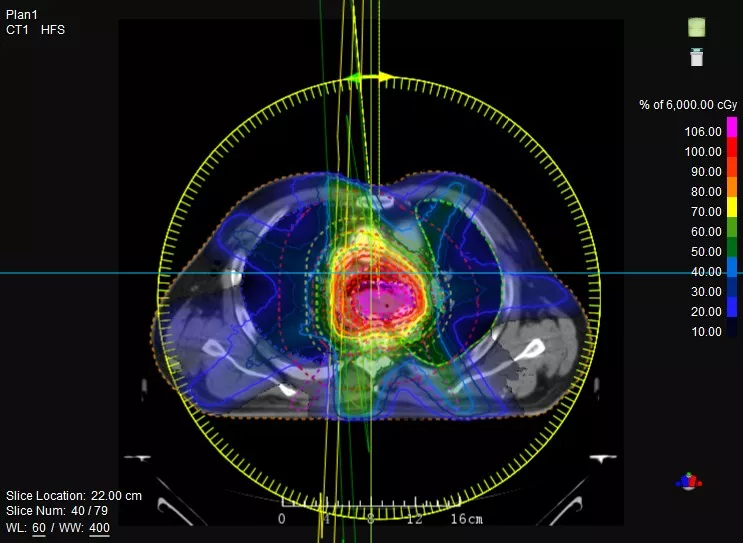

機(jī)載CT影像可直接用于放療計(jì)劃制作

CT-IGRT配準(zhǔn),除骨性標(biāo)記外,還能以器官、軟組織等作為參考,真正找到配準(zhǔn)目標(biāo)

鼻咽癌患者,進(jìn)行旋轉(zhuǎn)容積調(diào)強(qiáng)治療(uARC)